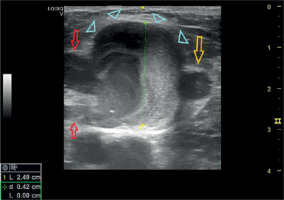

Figure 6

A focal dilatation of the right cephalic vein in a young patient representing a superficial venous aneurysm (light green arrow). He engages in regular resistance/weight training recreationally

Although there are no case reports describing VAs resulting from weightlifting so far, systematic weight training may be implicated in VA development. Exercise-induced increases in blood flow, venous return, and circulating volume promote increased venous diameter and compliance [82–84]. Elevated intraluminal pressure is a recognized contributor to venous degeneration and aneurysm formation; therefore, it is plausible that repeated strain from physical activity could contribute to venous aneurysm formation in predisposed individuals (Figure 6).

Two additional images from patients who presented in our clinic upon completion of this review are included (Figures 6 and 7). Although not analyzed extensively, they provide further insight and offer further illustrative value.